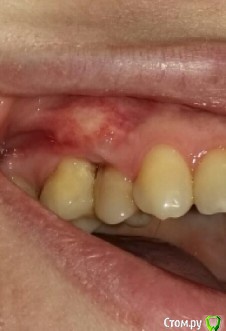

Фотографии начальной ситуации нет, первое фото уже после лоскутной операции и  пересадки  трансплантата с нёба с корональным смещением.

История такая - после ортодонтического лечения с удалением 15зуба образовалась рецессия, которая уходила все дальше и дальше и дальше. В успех мероприятия никто, кроме пациента не верил, первым этапом я отчистила поверхности корней и отполировала нависающие края пломб на контакте, очистила межзубный промежуток, в него только aPRF, натянула, ушила. С нёбной стороны дефект закрылся, отличный сосочек. Вестибулярно стало лучше, но  не фонтан.

Пересадила с нёба лоскут ( на первом фото).Неудачно, частично некротизировался, результат не достигнут.

Отрезала бугор, огромный ломоть, получили толщину тканей феерическую, с избытком таким, что глаз дергался, глядя на этот Эверест (второе фото). Гулять так гулять, подумала я и сделала следующее (на схеме) - расслоила этот бугор, сделав разрез выше края десны, все вокруг деэпителизировала, мобилизовала и натянула. И оно таки сработало! Последнее фото - 6 месяцев результату, продолжаем наблюдать. post-35757-0-84941800-1532674651_thumb.jpgpost-35757-0-82539900-1532674591_thumb.jpgpost-35757-0-09882000-1532674698_thumb.jpgpost-35757-0-47621300-1532674725_thumb.jpgpost-35757-0-64948100-1532674747_thumb.jpg